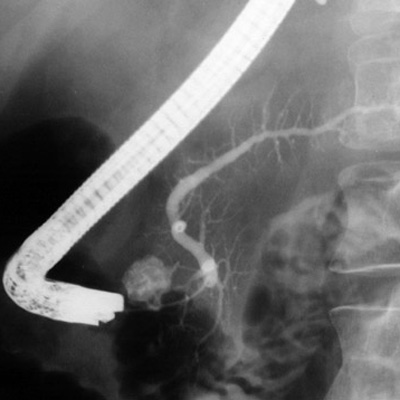

ERCP

Kronik Pancreatitisin nedeni eğer, safra veya pankreas kanalının daralması veya tıkanması veya psödokist olarak tanımlanması durumunda, endoskopik retrograd kolanjiyopankreatografi veya ERCP ile ileri terapötik endoskopi ile tedavi edilebilir. Bu işlemler kanalın genişletilmesi, kanalın açık kalması için bir stentin (içi boş bir tüp) yerleştirilmesi, bir safra kanalı darlığını tedavi etmek için bir sfinkterotomi ve stent yerleştirilmesi, kistin boşaltılması veya çıkarılmasını içerir. Tekrarlayan bir atak için önleyici tedbirler de hastalar için tavsiye edilir. Sigara ve alkollü içeceklerden ve fazla yağlı bir diyet yemekten kaçınmayı içerir.